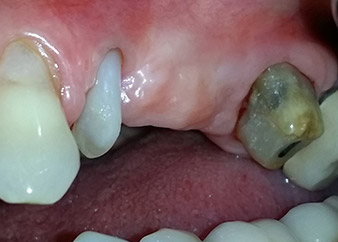

След един месец, в деня на операцията, болката и възпалението в зъб 24 е минимално, но подвижността в Miller class 2 е на лице. След отваряне на ламбата и почистването на периапикалната и перирадикуларната тъкани, обхватът на костния дефект стана очевиден (Фиг. 2 и 3).

В букалния корен, цялата вестибуларна и дистална кост липсва. Захващането е значително ограничено до палатиналния корен, подчертавайки предварително лошата прогноза. Зъб 27 също откри намалено хоризонтално захващане и минимално апикално разреждане (Фиг. 1) без клинични симптоми.